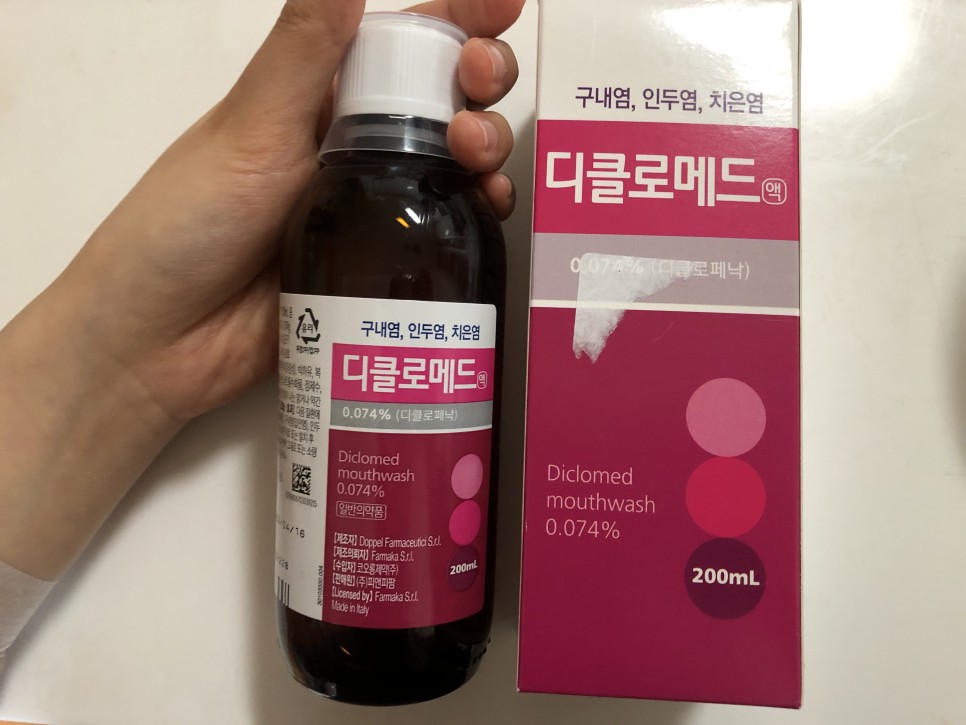

이건 수술하면 주는 우의약이지만 하루에 2~3회씩 양치질을 하고 토하면 돼요

얼음물의 가글은 통증 완화, 지혈 등의 목적이라면 소독이라고 말씀하셨습니다!